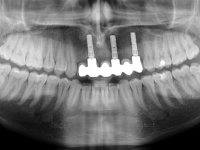

Foi aconselhada a extracção dos dentes 12 e 11 e esperar mais 3 meses para se conseguir uma completa cicatrização da zona. Estabilizada a situação fazer-se –ia um enceramento de diagnóstico que dando origem a uma guia imagiológica permitiria fazer uma TAC. em que o posicionamento idealizado dos dentes pudesse ser relacionado com o património ósseo. O objectivo seria fazer uma ponte cerâmica implanto suportada.

O paciente foi observado conjuntamente e a dúvida que surgiu de imediato foi se seria possível com a regeneração óssea a efectuar poder ser reabilitada naturalmente a zona das papilas interdentárias. Nesse sentido foi feito um enceramento de diagnóstico que contemplaria as duas hipóteses, utilizando ou não a cerâmica gengival. A confecção desse enceramento foi fundamental para expor ao paciente a dificuldade da reabilitação. O wax-up deu origem a um mock-up que foi aprovado pelo paciente e que simultaneamente serviu de guia imagiológica. O caso foi planificado cirurgicamente e realizada uma guia cirúrgica com que foram colocados os implantes. Após 10 semanas foi feita a 1ª impressão para confecção da ponte provisória. Foram criados os primeiros perfis de emergência na gengiva artificial e foi digitalizado o modelo. Por processo de CAD-CAM foi confeccionada uma ponte provisória aparafusada baseada no enceramento de diagnóstico. A ponte trabalhou durante 8 semanas os tecidos moles que foram fielmente copiados numa impressão com técnica de moldeira aberta. Os transferes foram individualizados com resina composta para copiarem fielmente os perfis de emergência criados pela ponte provisória. Confeccionado o modelo de trabalho definitivo, foi realizada uma infra-estrutura em zircónio seguindo a orientação do enceramento de diagnóstico. O assentamento da infra-estrutura foi testado em boca e simultaneamente foi novamente impressionados os tecidos moles com um silicone fluido. Nessa consulta foi feito o levantamento da cor. Os dentes 13 e 23 apresentavam uma saturação anormalmente forte que resolvemos não valorizar, optando por privilegiar a relação com o sector antero-inferior. Foi realizada uma nova gengiva artificial com a impressão que acompanhou a impressão de arrasto com a infra-estrutura. Após a colocação da cerâmica na infra-estrutura foram coladas as meso-estruturas. O trabalho final foi aparafusado lentamente permitindo a adaptação dos tecidos moles.